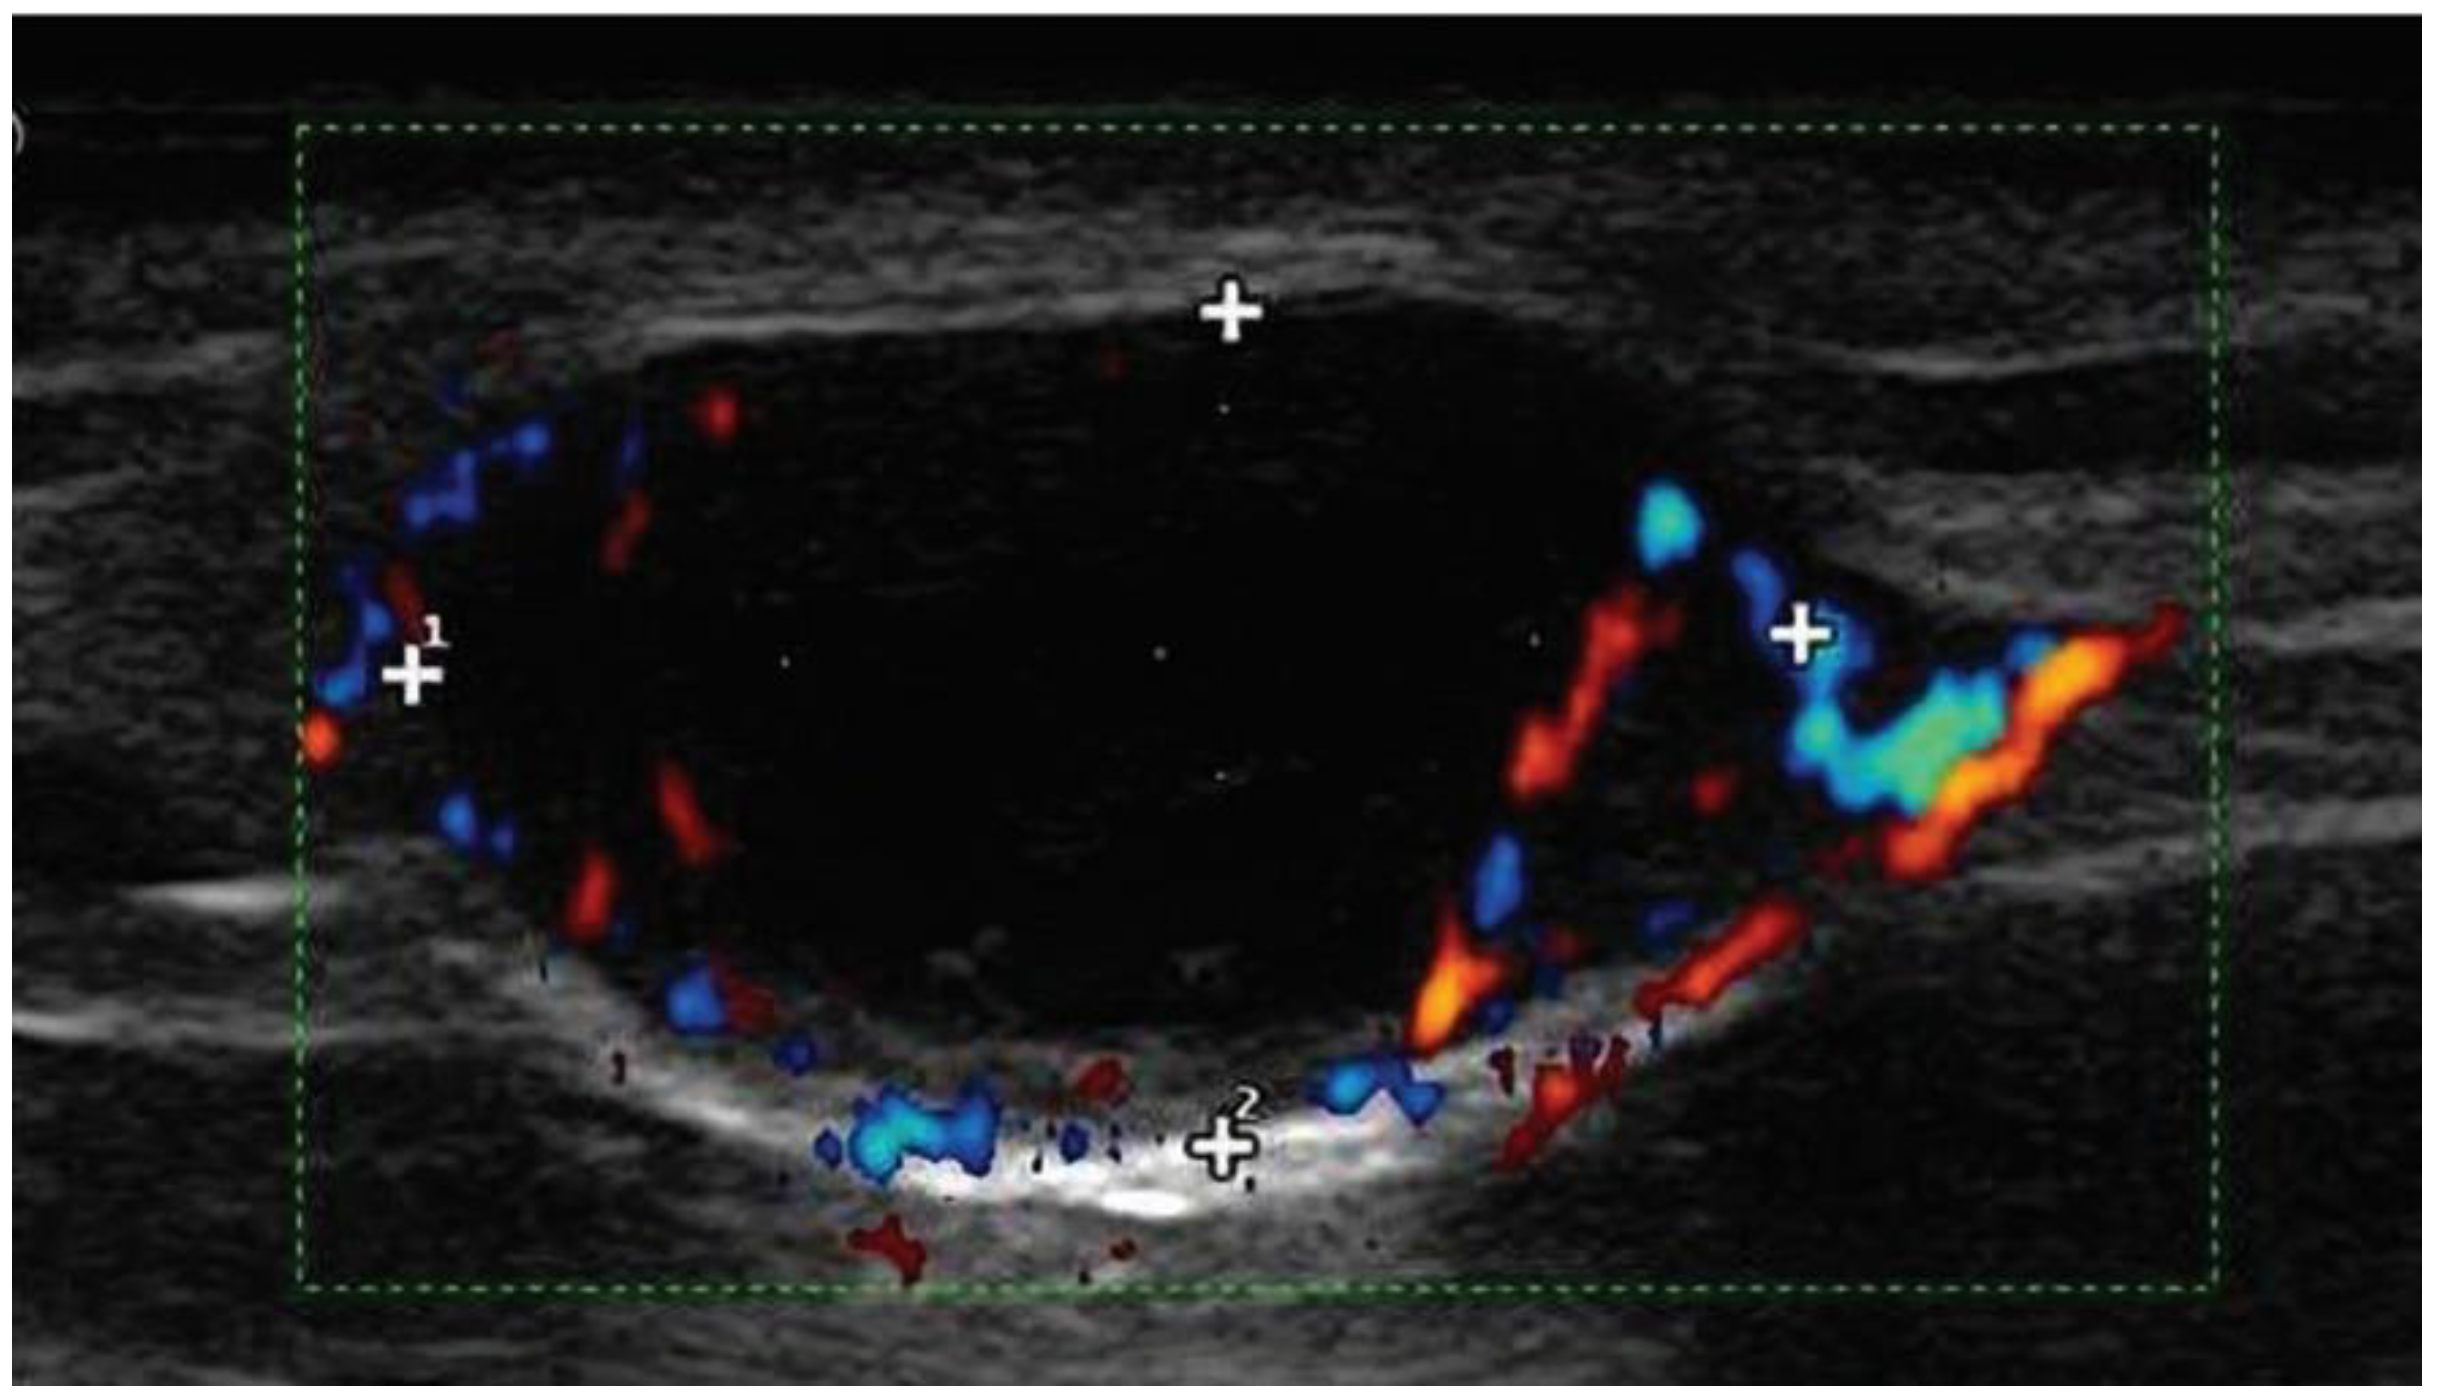

11.1. Ultrasounds of Nodal Basins